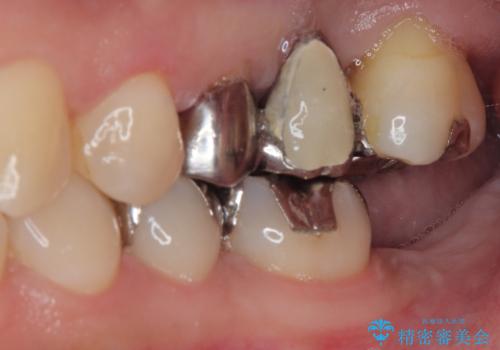

- 前歯の部分矯正や仮歯に置き換えるなど、治療途中のまま放置してしまったとのことで来院された患者様です。

骨格的に下顎骨が前方にあり、歯列の幅も下顎の方が大きいため、奥歯に負担のかかりやすい咬合でした。

大臼歯部は、上下左右ともに咬合により問題が生じており、骨格的な問題から積極的な治療をするべきか判断の難しい状況でした。

臼歯部は痛みが生じている歯に絞って処置を行い、それ以外については手を加えず、現状維持を心がけることとしました。

前歯部については抜歯が必要な歯を抜歯し、インプラントやブリッジなどにより補綴治療を行うこととしました。

臼歯部は今後抜歯が必要となった際に、インプラントにより咬合を構築していくこととしました。今回の治療においても、今後の臼歯部の治療に対応できるよう治療計画を立案しています。